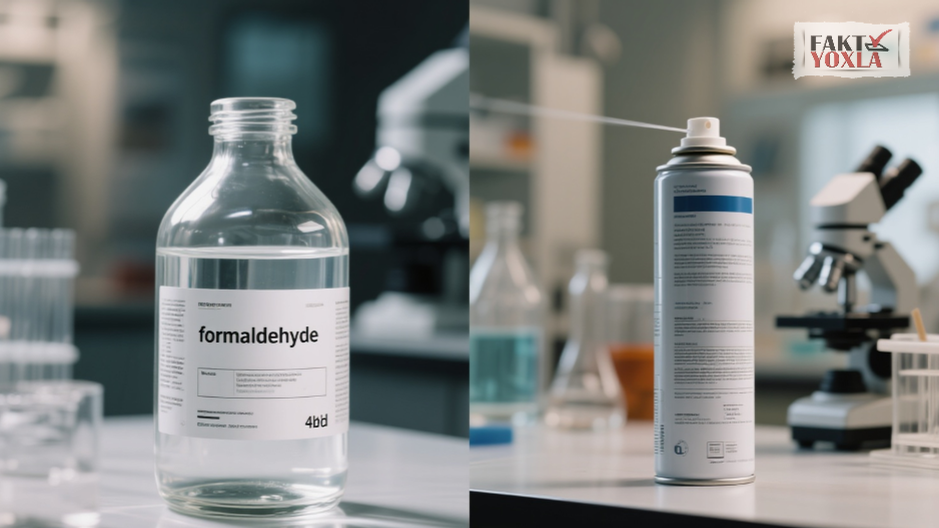

- Kanserojenler: Kansere neden olabilen kimyasallar (örneğin, ısıtma sırasında sıvı bileşenlerin parçalanmasıyla oluşan formaldehit).

Gliserinin termal ayrışma ürünleri (akrolein ve formaldehit gibi) ve kimyasal aromalı maddeler enflamasyonu ve hücresel mutasyonları tetikleyebilir.